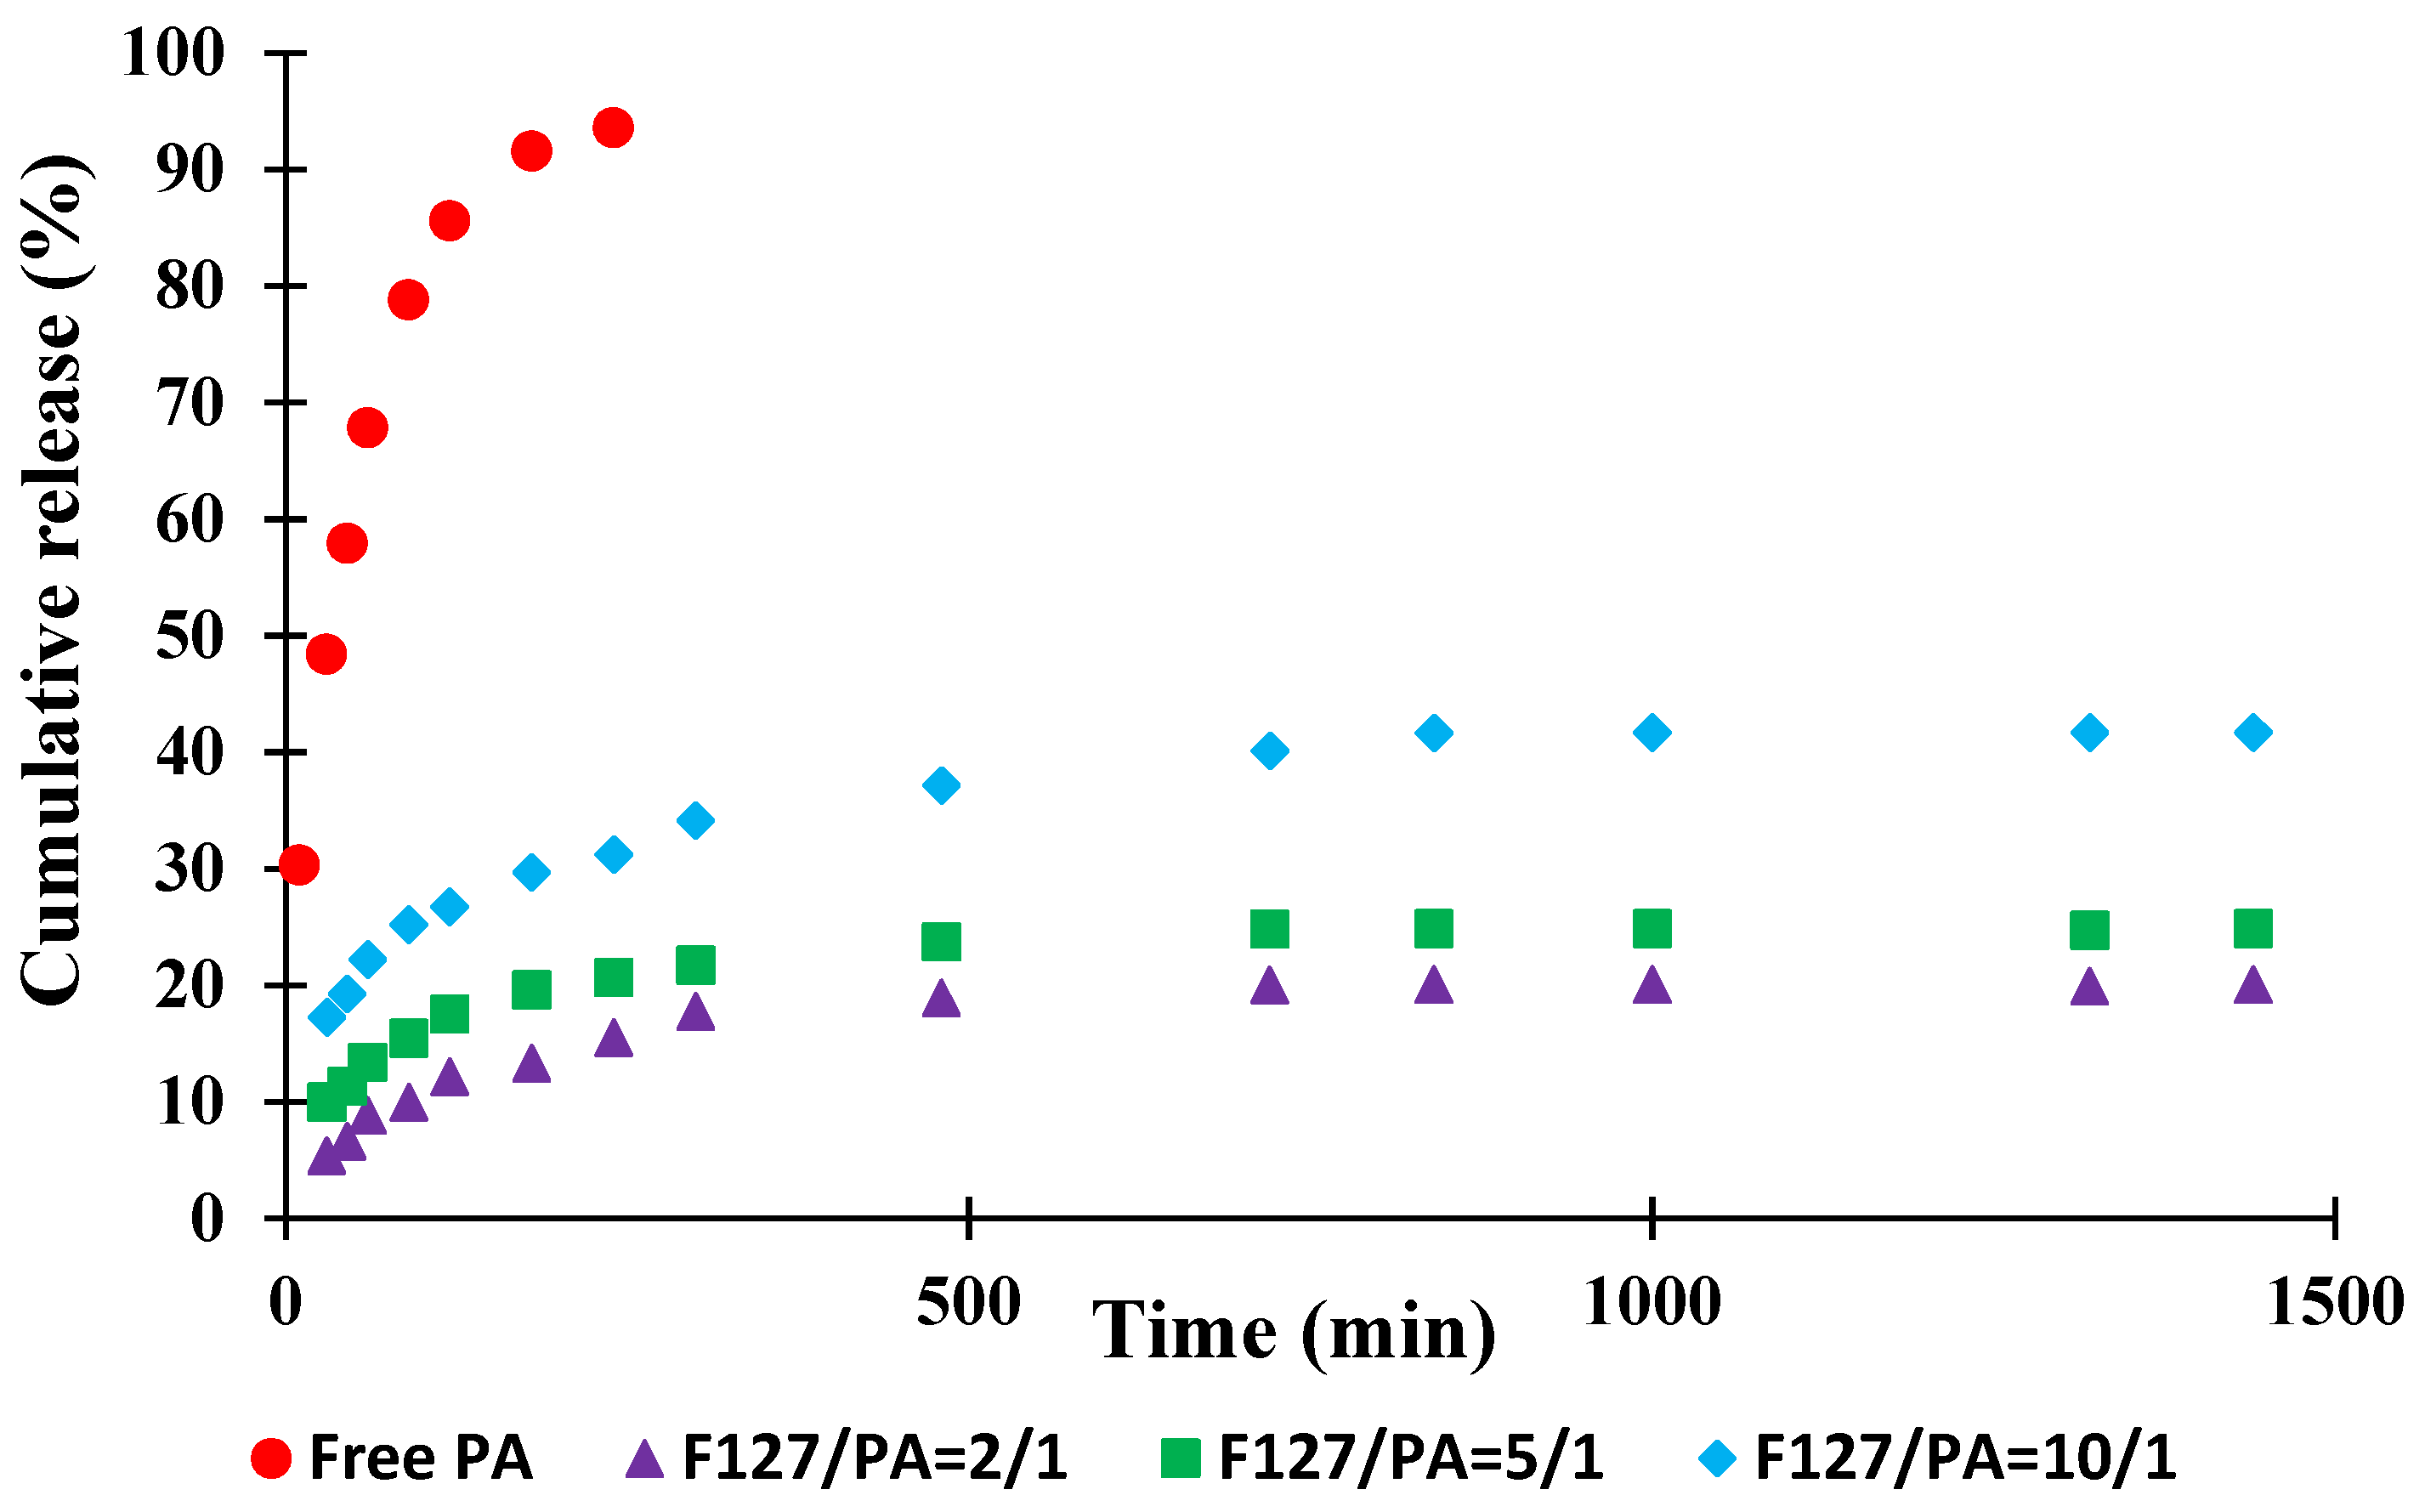

3.2. Drug Encapsulation Efficiencies

| F127/API Ratio (% w/w) | DEE (%) | DLE (%) |

|---|---|---|

| 10/1 | 84.8 | 11.1 |

| 5/1 | 66.6 | 10.3 |

| 2/1 | 30.9 | 7.7 |